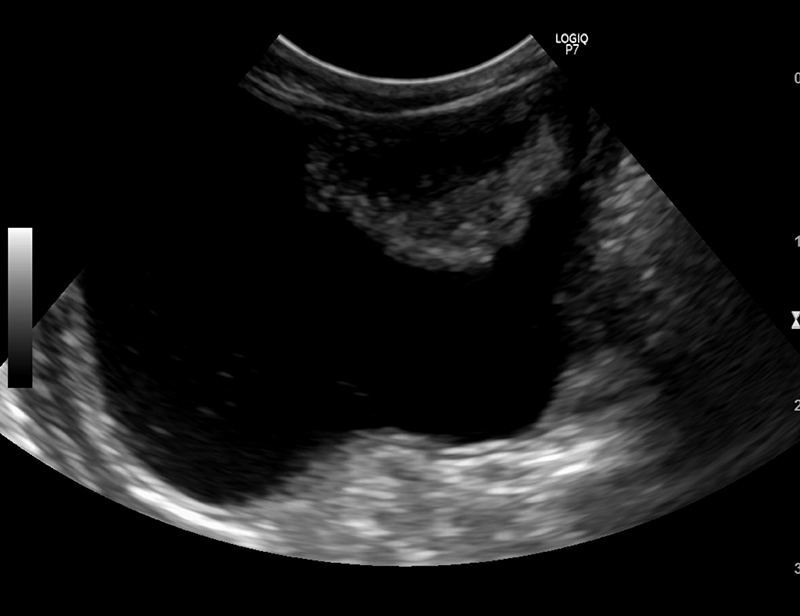

診断は超音波検査が有効です。

膀胱の中に明確な腫瘤が発見できることが多く、腫瘤の発生している部位、膀胱壁や尿管・尿道への浸潤具合、さら

に腎臓や付近のリンパ節の評価も行います。

ただし、膀胱炎でも膀胱の粘膜が肥厚したり、移行上皮癌以外にも良性の炎症性ポリープなどが発生することもある

ため超音波検査だけで移行上皮癌の診断はできません。